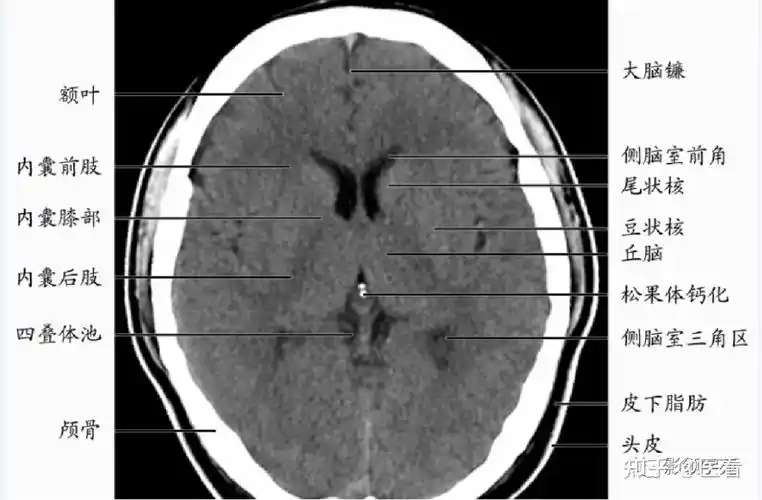

双侧基底节区对称性病变